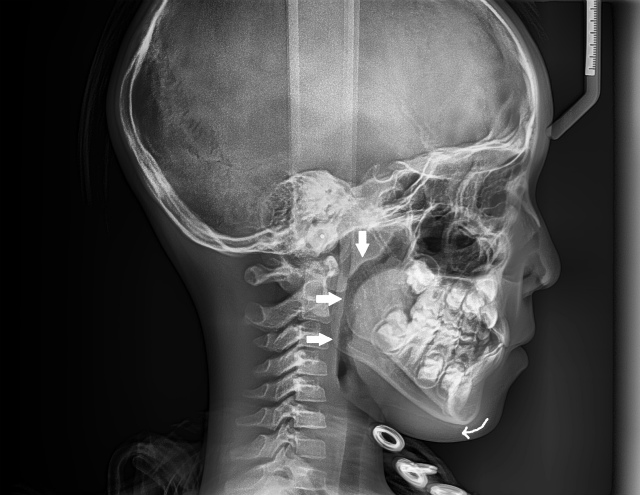

オトガイの矢印は下顎骨の後方回転を示す。気道が全体で狭くなっている (10代半ば男性)